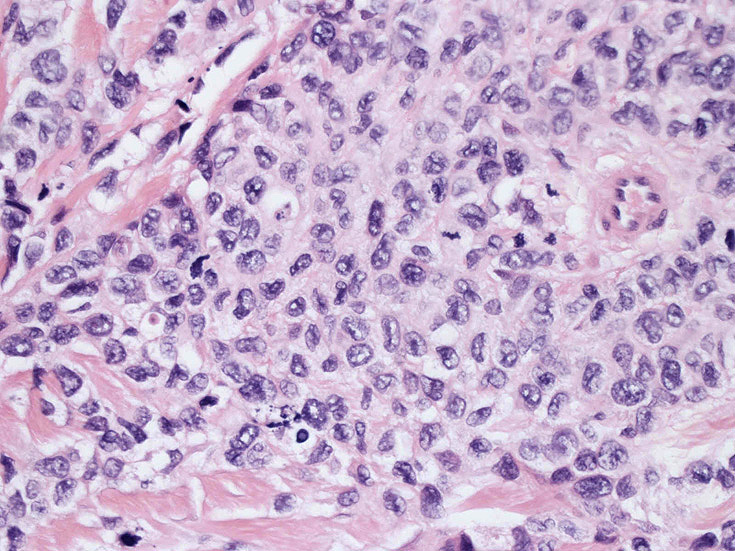

皮膚に異型細胞の浸潤がみられる。異型細胞は表皮内に浸潤するほか、表皮真皮境界部, 真皮, 皮下脂肪組織にもびまん, 結節様の浸潤所見を示す。血管周囲に浸潤、集蔟する所見も多く見られる。 増殖浸潤細胞の核には類円形や腎臓形, またはへこみ, 切れ込み, 溝などを有する多型な核が認められる。クロマチンは粗でvesicularな核が多い。核小体の明らかな核もある。好エオジン性の核内封入体様構造も少数に見られた。mitosisは容易に認められる。hyperchromaticな多型核, bizzarreな細胞が高頻度に認められ異型度は高いと考えられる。細胞質は境界不明瞭, 淡明または泡沫様の 好エオジン性胞体である。

免疫染色 浸潤細胞はCD1a+, S100+, Langerin+, HLA-DR+, CD4+, CD45+, CD68+. MIB-1 index:24.4%